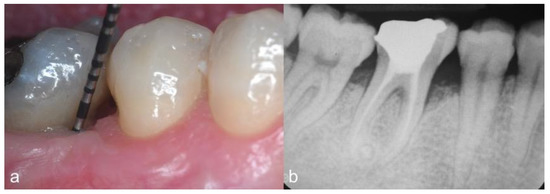

2. Case Series

2.2. Clinical Findings

2.4. Follow-Up and Outcomes